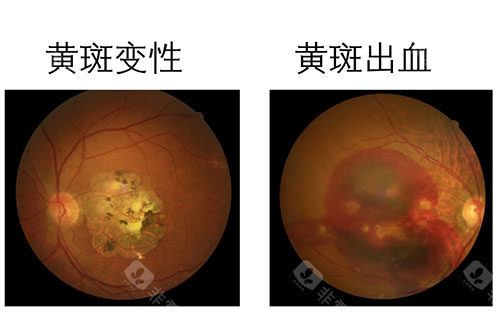

黄斑病变:老年性黄斑变性、黄斑裂孔、黄斑前膜、中心性浆液性脉络膜视网膜病变等

特别值得一提的是,雷医生在黄斑病变的治疗方面具有丰富经验,能够为患者提供从药物注射到手术治疗的全套解决方案。

实例一:65岁男性患者,因"右眼视力突然下降伴视物变形"就诊。经检查确诊为右眼黄斑裂孔,视力仅0.1。雷医生为其进行了小创口玻璃体切割联合内界膜剥除手术,术后3个月复查,黄斑裂孔闭合,视力修复至0.6。

实例二:42岁女性糖尿病患者,因"双眼视力逐渐下降"就诊。检查发现双眼严峻的糖尿病视网膜病变伴黄斑水肿。雷医生为其制定了系统的治疗方案,包括视网膜激光治疗和抗VEGF药物玻璃体腔注射。经过6个月治疗,患者视力稳定,黄斑水肿明显减轻。